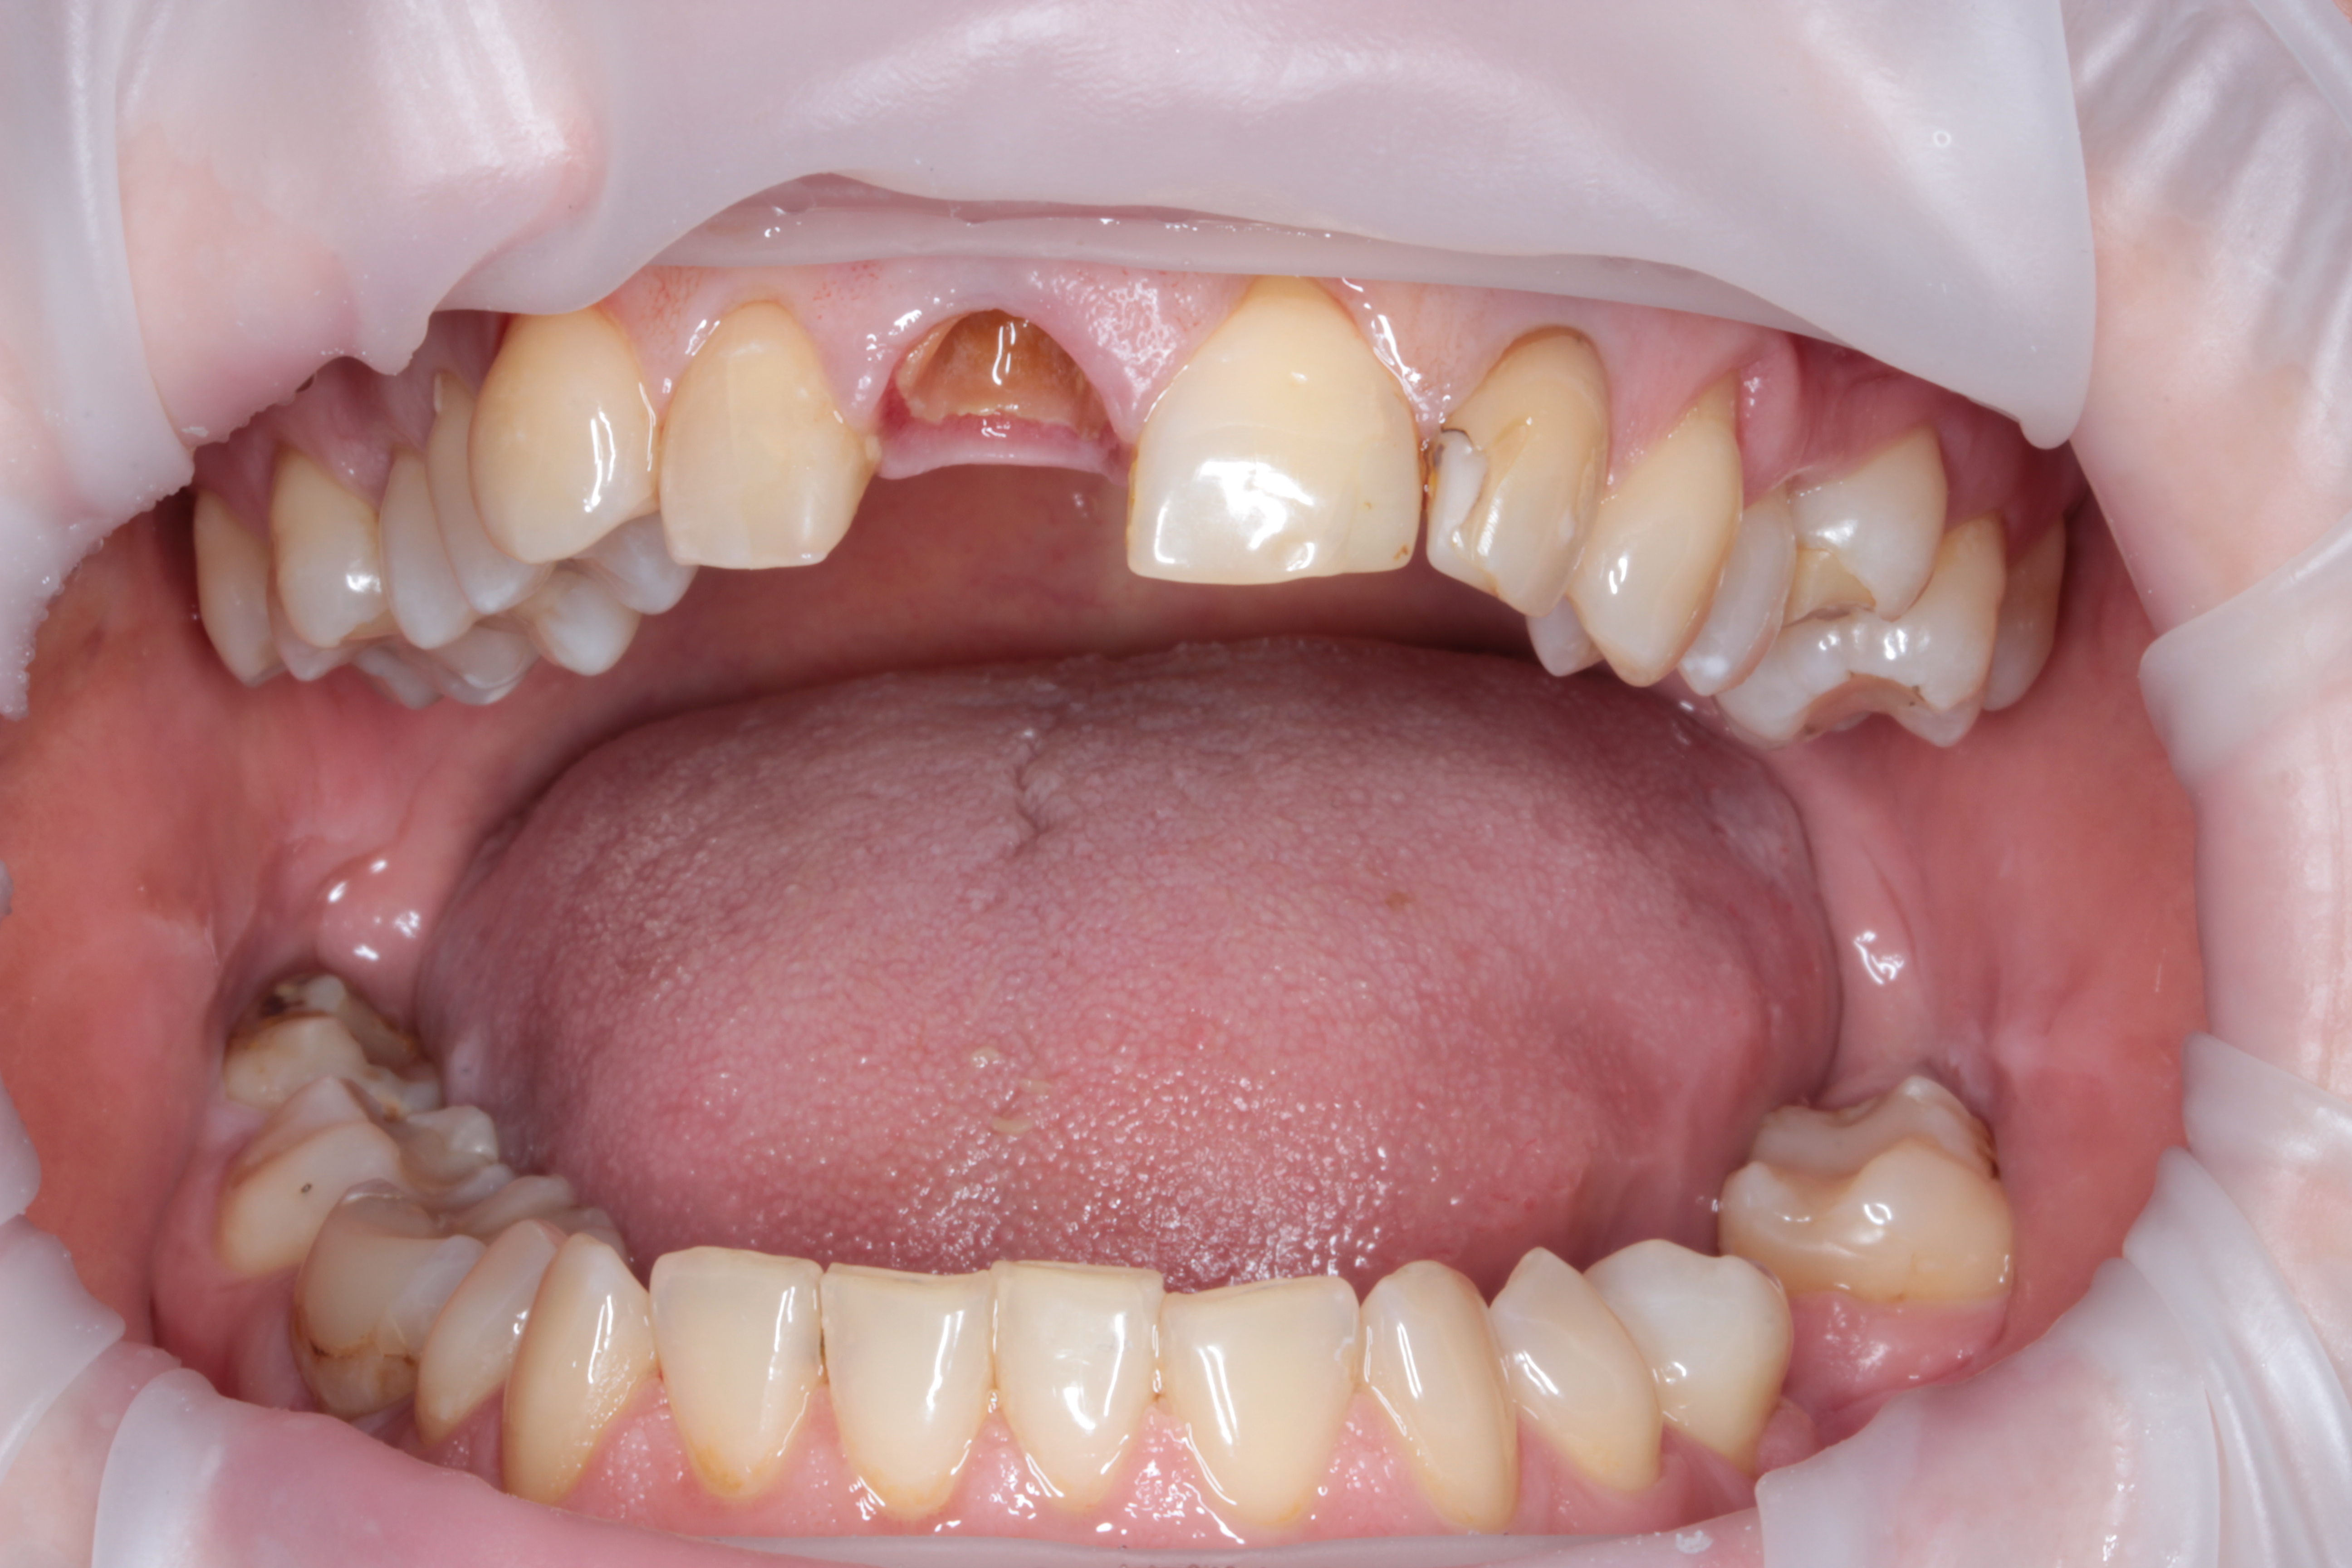

Зуб был атравматически удален фрагментированием на части с помощью пьезохирургического аппарата и элеватора для максимального сохранения объема костной ткани в месте будущей дентальной имплантации. Во время экстракции врач сохранил целостность вестибулярной стенки альвеолы. Восстановление дефекта мягких тканей в данной области проводилось при помощи туннельной технологии субэпителиальным небным десневым трансплантатом . Устранение дефекта слизистой оболочки и десен способствует стабильному высокоэстетическому результату лечения. После этого хирург осуществляет наращивание костной ткани в вестибулярной области с использованием твердых частиц остеопластического материала. Для предотвращения попадания костного материала на внутреннюю часть имплантата врач устанавливает формирователь десны. Учитывая то, что пациентка по профессии учитель и впереди у нее было много ответственных мероприятий, было принято решение изготовить временную коронку на дентальный имплант непосредственно во время операции, так как все необходимые для этого условия были соблюдены и была такая возможность для этого.

Рис. 2. Вид пациентки после всех проведенных манипуляций в первое посещение.